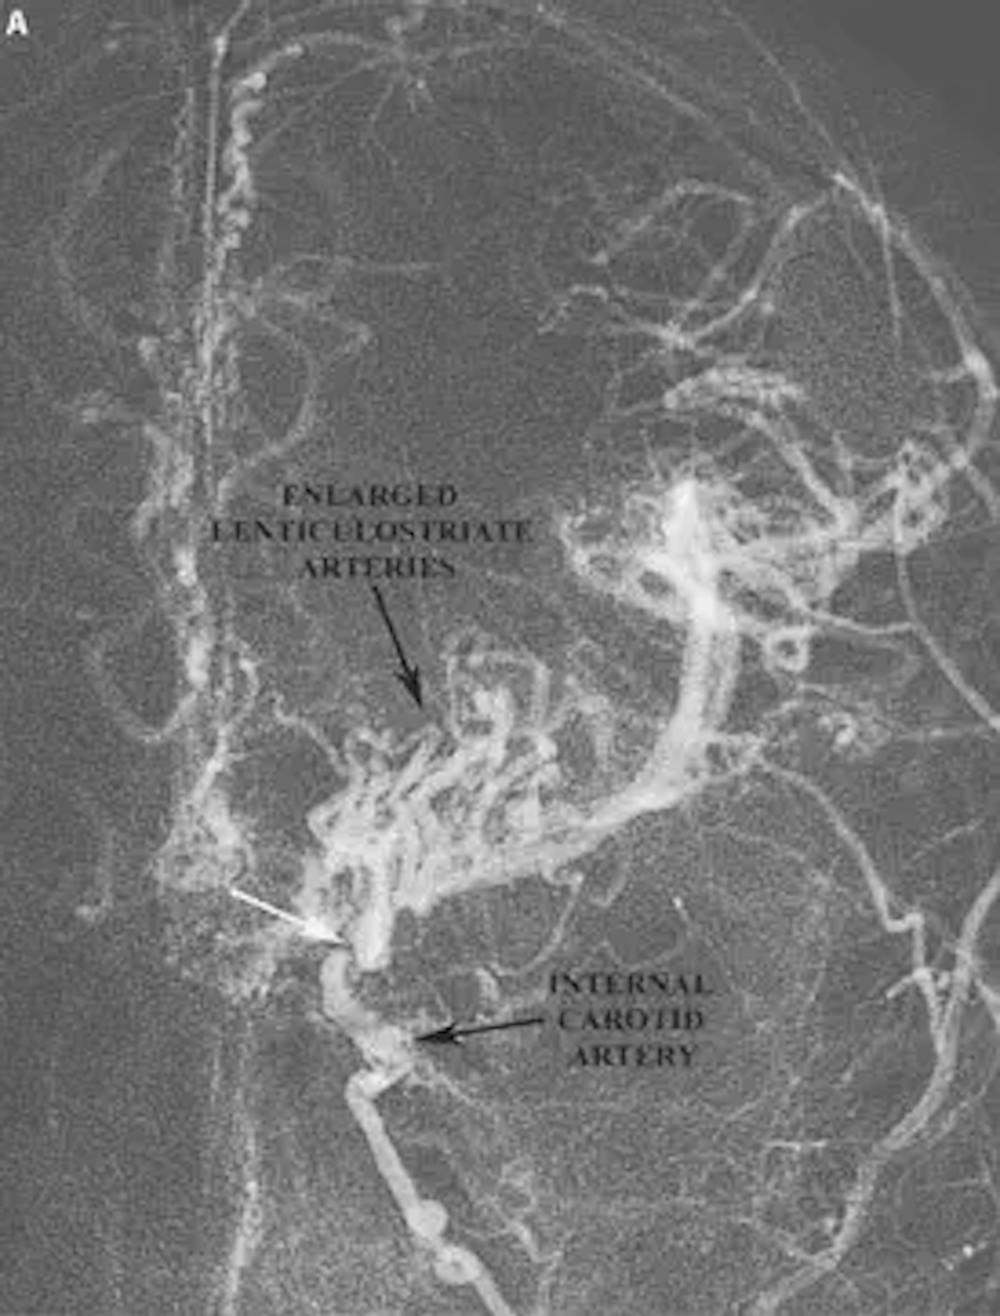

A) Angiographie AP préopératoire montrant les caractéristiques de la maladie de Moya-Moya. Notez l’aspect déchiqueté de l’artère carotide interne ainsi que la région où l’artère carotide interne est occluse (flèche blanche). Notez également les très grosses artères lenticulostriées qui ressemblent à des volutes ou des bouffées de fumée s’élevant dans l’air.

La maladie de Moya moya est typiquement rencontrée dans deux groupes de patients : 1) Les enfants de moins de dix ans et 2) Adultes dans leur troisième décennie de vie. La maladie de Moya moya chez l’enfant se manifeste typiquement par des accidents vasculaires cérébraux non hémorragiques et des crises d’épilepsie. Dans la population adulte, cependant, moya moya se manifeste plus souvent par des hémorragies cérébrales. Les anévrismes cérébraux sont également fréquents chez les patients atteints de la maladie de moya moya, et la rupture des anévrismes peut expliquer les hémorragies cérébrales chez certains patients. Une fois suspecté, le diagnostic de la maladie de moya moya est confirmé par une angiographie cérébrale. L’angiographie montre souvent une occlusion des artères carotides avec un petit réseau de vaisseaux sanguins à la base du cerveau ressemblant à une “bouffée de fumée”.